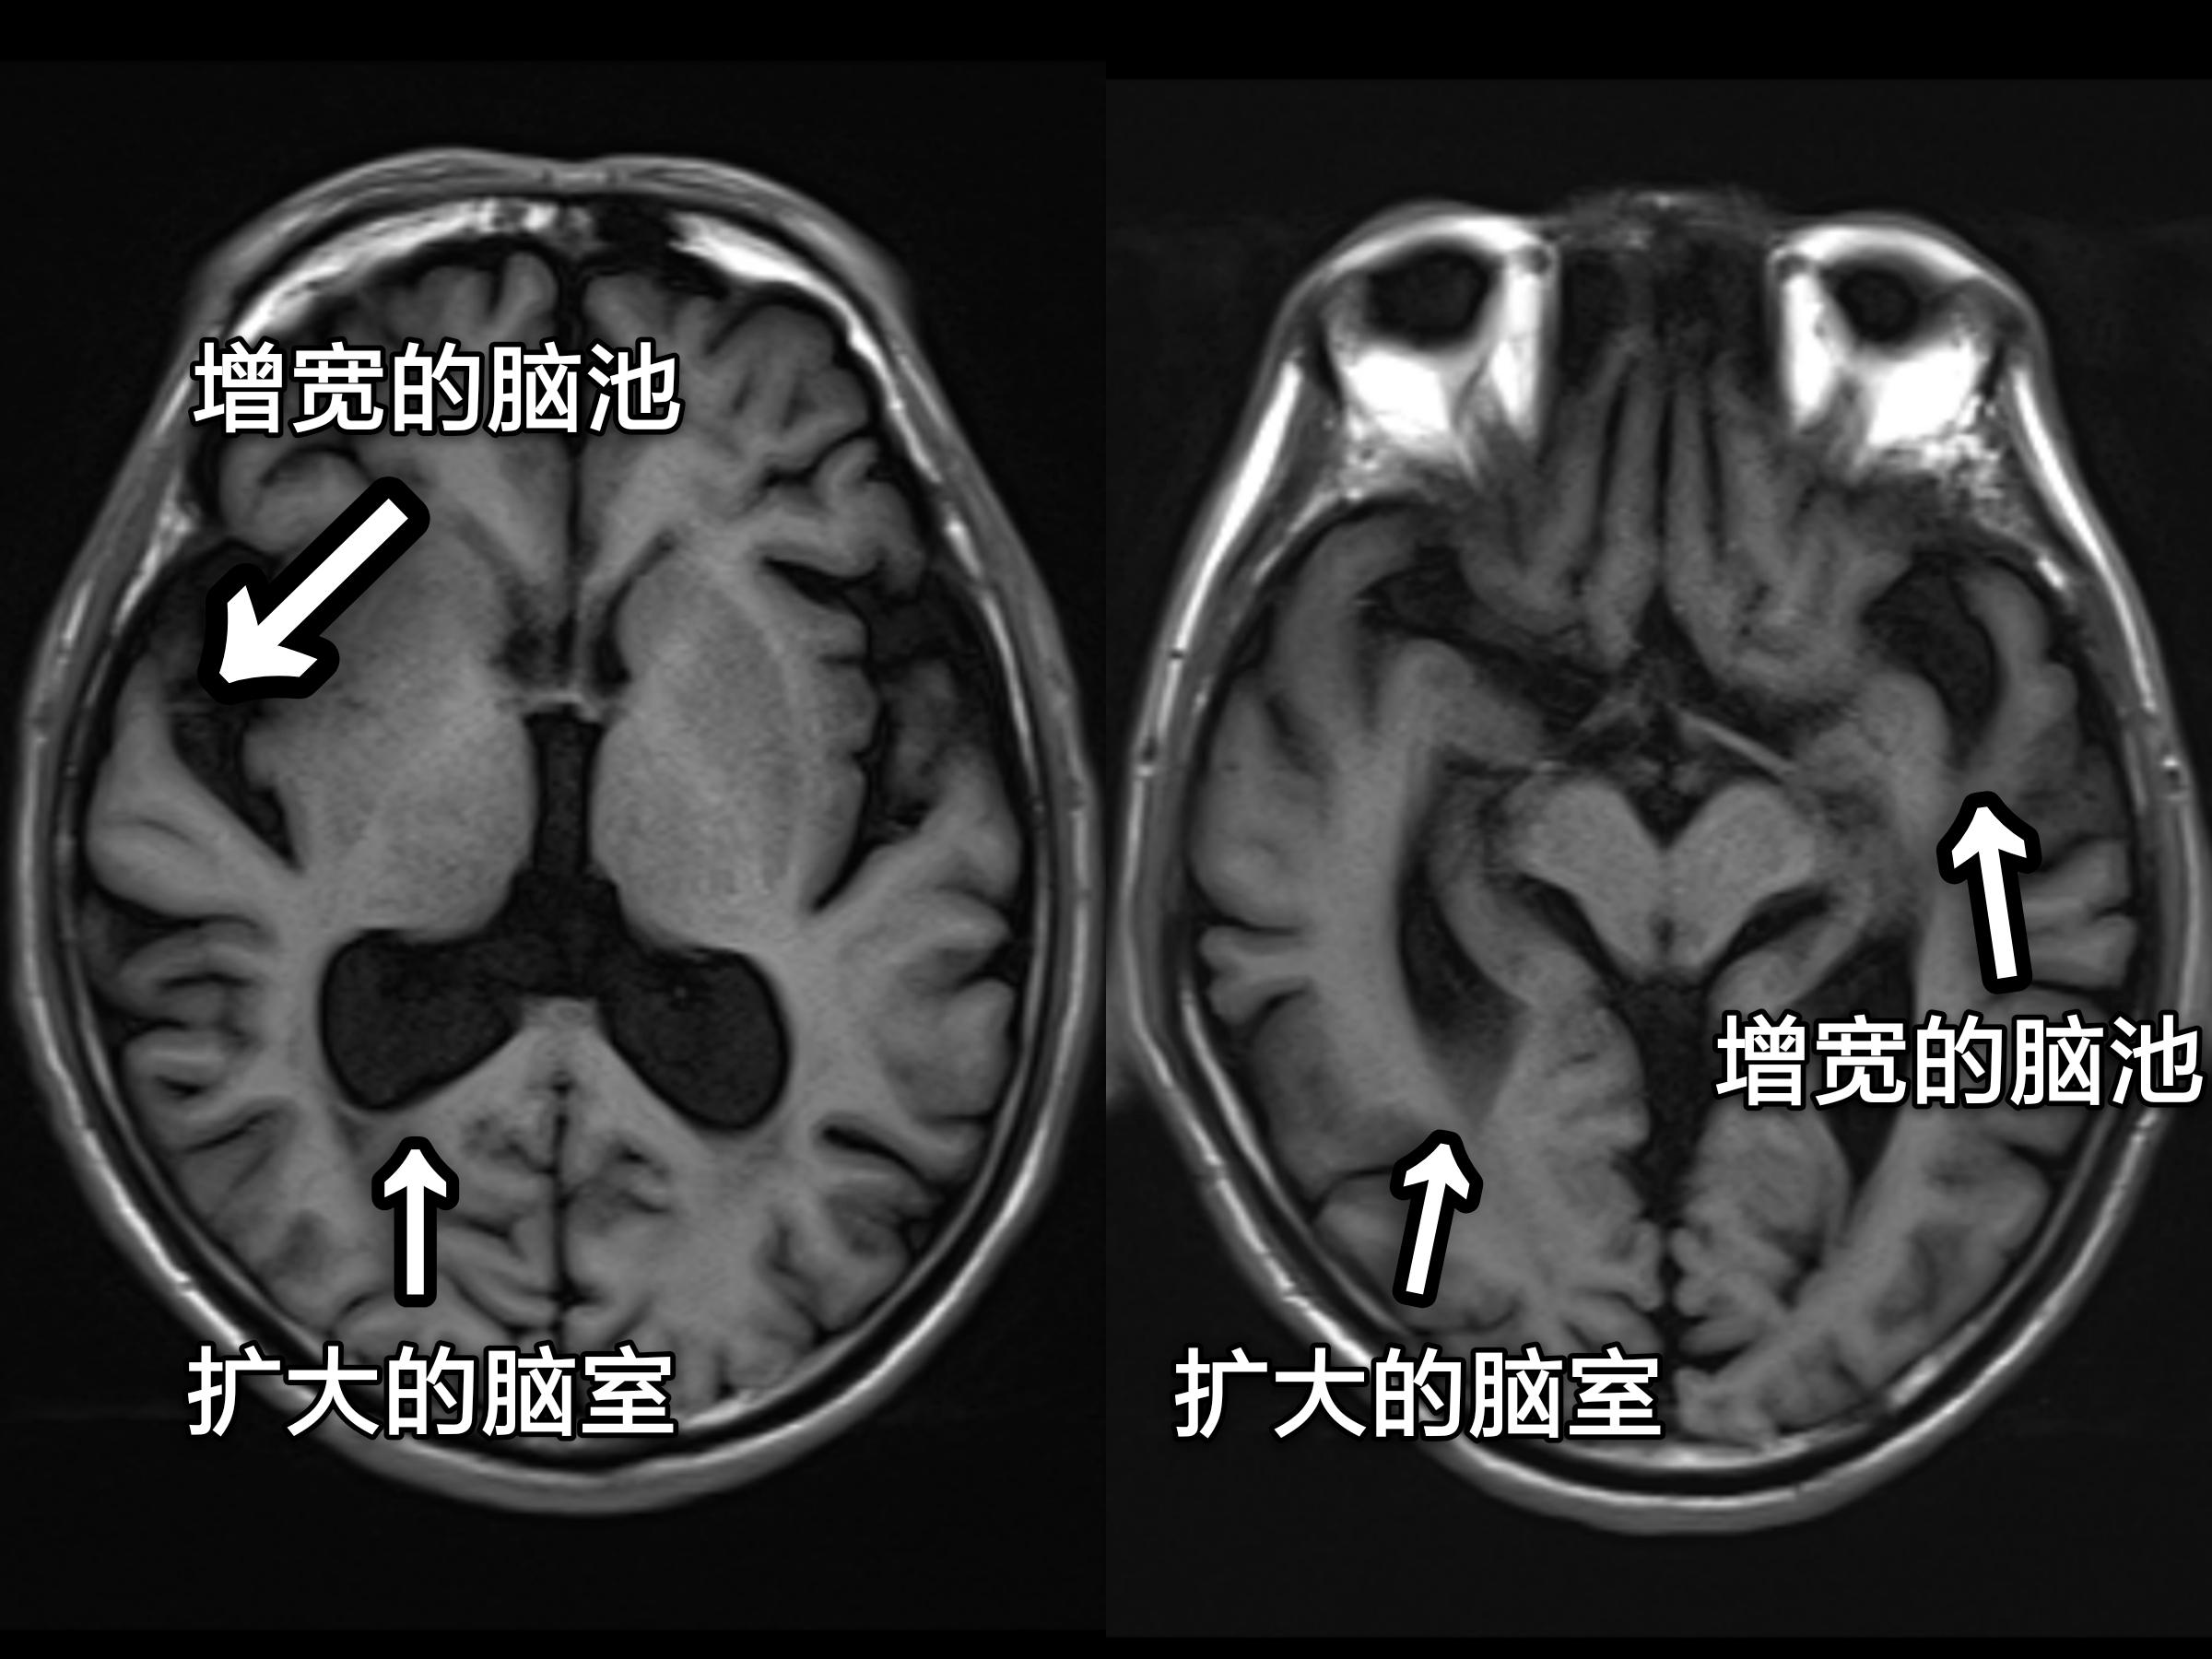

再来看看脑萎缩的图像(箭头所标处):

MRI检查萎缩的大脑

从上面的这几幅图中,大家可以明显看出脑室、脑池的扩大和脑沟增宽增深,脑回变窄。